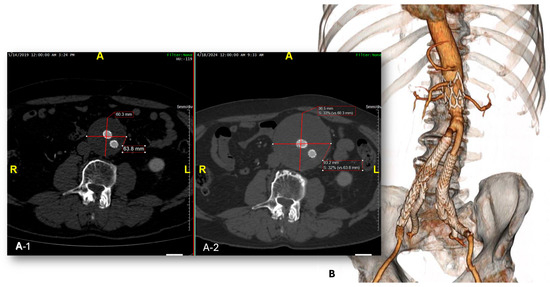

Figure 2. Control CTA showing evident enlargement of the aneurysmal sac due to type II endoleak (A1,A2). Partial surgical conversion with explantation of the endograft main body and preservation of the iliac side branches at 103 months after the index procedure (B).

During the follow-up period, three complete and one partial conversion were performed at 4, 36, 103, and 114 months after the index procedure, respectively (Figure 2).

In all cases, a growth of the residual aneurysmal sac due to a type II endoleak was detected. The early conversion at 4 months was performed in an emergency setting due to a contained rupture of the residual aneurysmal sac. Indications for reintervention are reported in Table 4.